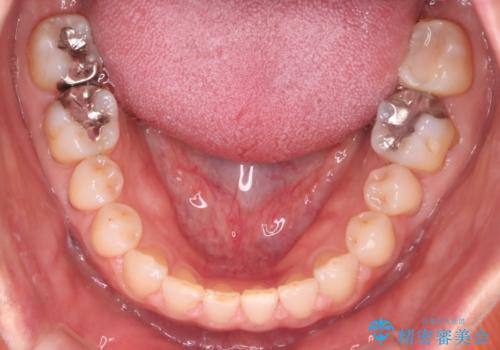

- 前歯のすきっ歯が気になるということで来院されました。今回は抜歯はしないためワイヤー矯正かインビザライン矯正のどちらでも治療可能でしたが、患者さまのご希望により表のワイヤー装置にて治療をおこないました。

前歯に隙間がいくつかあったため、今回は上下でゴムかけを行いスペースを埋めるための力をかけて閉じました。もう少し早く終了する予定でしたが、ブラッシング不良による歯肉腫脹があり、一部スペースクローズに時間がかかりました。